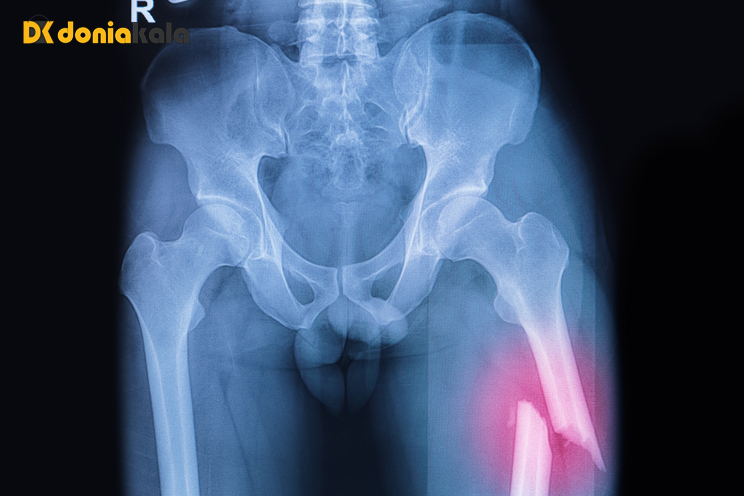

شکستگی باز (شکستگی که در آن استخوان از طریق پوست عبور می کند تا بتوانید آن را ببینید یا زخم عمیقی که استخوان را از طریق پوست نمایان می کند) یک اورژانس در نظر گرفته می شود. برای این نوع شکستگی فورا مراقبت های پزشکی را دریافت کنید. هر گونه آسیب به استخوان های ستون فقرات نیز یک اورژانس پزشکی است. اینها باعث کمردرد شدید می شوند و ممکن است باعث مشکلات عصبی شوند. اینها شامل بی حسی، سوزن سوزن شدن، ضعف یا مشکلات روده و مثانه است. اگر فکر می کنید کسی در استخوان های ستون فقراتش شکسته است با آژانس تماس بگیرید.

شکستگی شکستگی جزئی یا کامل در استخوان است. انواع مختلفی از شکستگی ها وجود دارد. شکستگی استخوان اغلب در اثر افتادن، آسیب، یا به دلیل ضربه یا ضربه مستقیم به بدن ایجاد می شود. استفاده بیش از حد یا حرکات تکراری می تواند باعث شکستگی استرس شود. همچنین بیماری هایی که استخوان را ضعیف می کنند نیز می توانند. علائم شامل درد ناگهانی، تورم، و مشکل در استفاده یا حرکت دادن ناحیه آسیب دیده است. هدف اصلی درمان این است که قطعات استخوان را در جای خود قرار دهیم تا استخوان بهبود یابد. این را می توان با آتل، گچ گیری، جراحی یا کشش انجام داد. هر زمان که فکر می کنید ممکن است استخوان شکسته ای داشته باشید به یک ارائه دهنده مراقبت های بهداشتی مراجعه کنید.